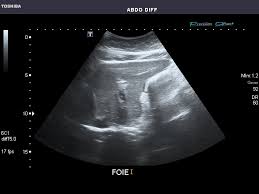

복부 초음파는 비침습적이며 방사선 노출이 없는 안전한 검사 방법으로, 초음파(ultrasound)를 통해 복부 내 장기들의 상태를 실시간으로 확인할 수 있는 진단 도구입니다. 복부 초음파로 알 수 있는 것 중에서는 특히 간, 담낭, 췌장, 비장, 신장, 방광, 대동맥, 소장, 대장 등의 상태를 파악할 수 있으며, 질환의 조기 발견에 탁월한 효과를 보입니다.

복부 초음파 검사는 위험 부담이 적고 간편하면서도 복부 내 장기들의 상태를 파악할 수 있는 매우 유용한 검사입니다. 특히 간, 담낭, 췌장, 신장 등의 질환을 조기에 진단하고 치료할 수 있어, 증상이 있을 때는 반드시 검사하는 것이 좋습니다. 또한, 만성 간질환자나 고위험군은 정기적인 초음파 검사를 통해 암 등의 심각한 질환을 예방할 수 있습니다.